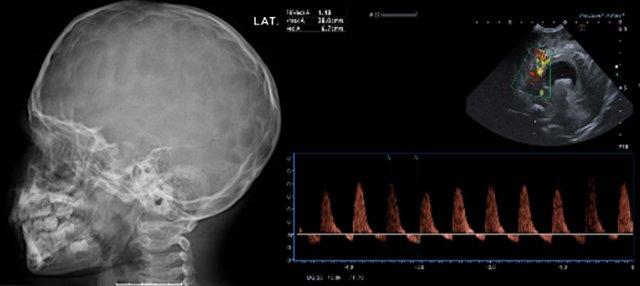

Khi nghi ngờ có dính khớp sọ sớm, phương tiện chẩn đoán hình ảnh đầu tay sẽ là siêu âm hoặc X-quang, tùy thuộc vào kinh nghiệm và sở thích của từng cơ sở y tế.

Do không có bức xạ ion hóa, siêu âm là phương pháp được ưu tiên lựa chọn.

Trong trường hợp nghi ngờ lâm sàng cao, CT 3D liều thấp được ưu tiên hơn.

Hình ảnh minh họa siêu âm của một đường khớp bình thường, hẹp đường khớp vành một bên và hẹp đường khớp dọc giữa kèm gờ xương.

X-quang sọ cho thấy các đường khớp còn mở.

Cần lưu ý rằng X-quang có giá trị hạn chế trong việc đánh giá đường khớp dọc giữa, và tình trạng đóng khớp một phần của đường khớp này có thể bị bỏ sót.

Tăng áp lực nội sọ.

TRÁI: Các vết ấn lõm trên phim X-quang sọ có độ nhạy thấp, đặc biệt ở trẻ nhỏ, nhưng khi xuất hiện, chúng rất gợi ý tình trạng tăng áp lực nội sọ.

PHẢI: Não úng thủy với dòng chảy tâm trương đảo ngược, biểu hiện của tăng áp lực nội sọ.